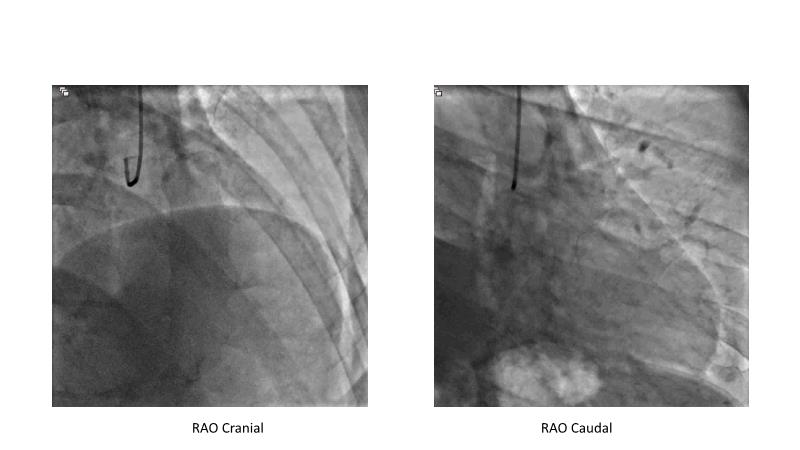

This session is recommended for you if you are seeking insights into the advantages of using IVUS imaging over visual assessment for better outcomes in left main bifurcation procedures. Discuss with experts the benefits of using RotaCUT in lesion preparation for left main bifurcation and explore the impact of high radial strength stents on the procedure's success.

• To understand why the use of IVUS imaging is different from seeing with experienced eyes to achieve improved left main bifurcation outcome

• To see advantages of RotaCUT as part of lesion preparation in left main bifurcation